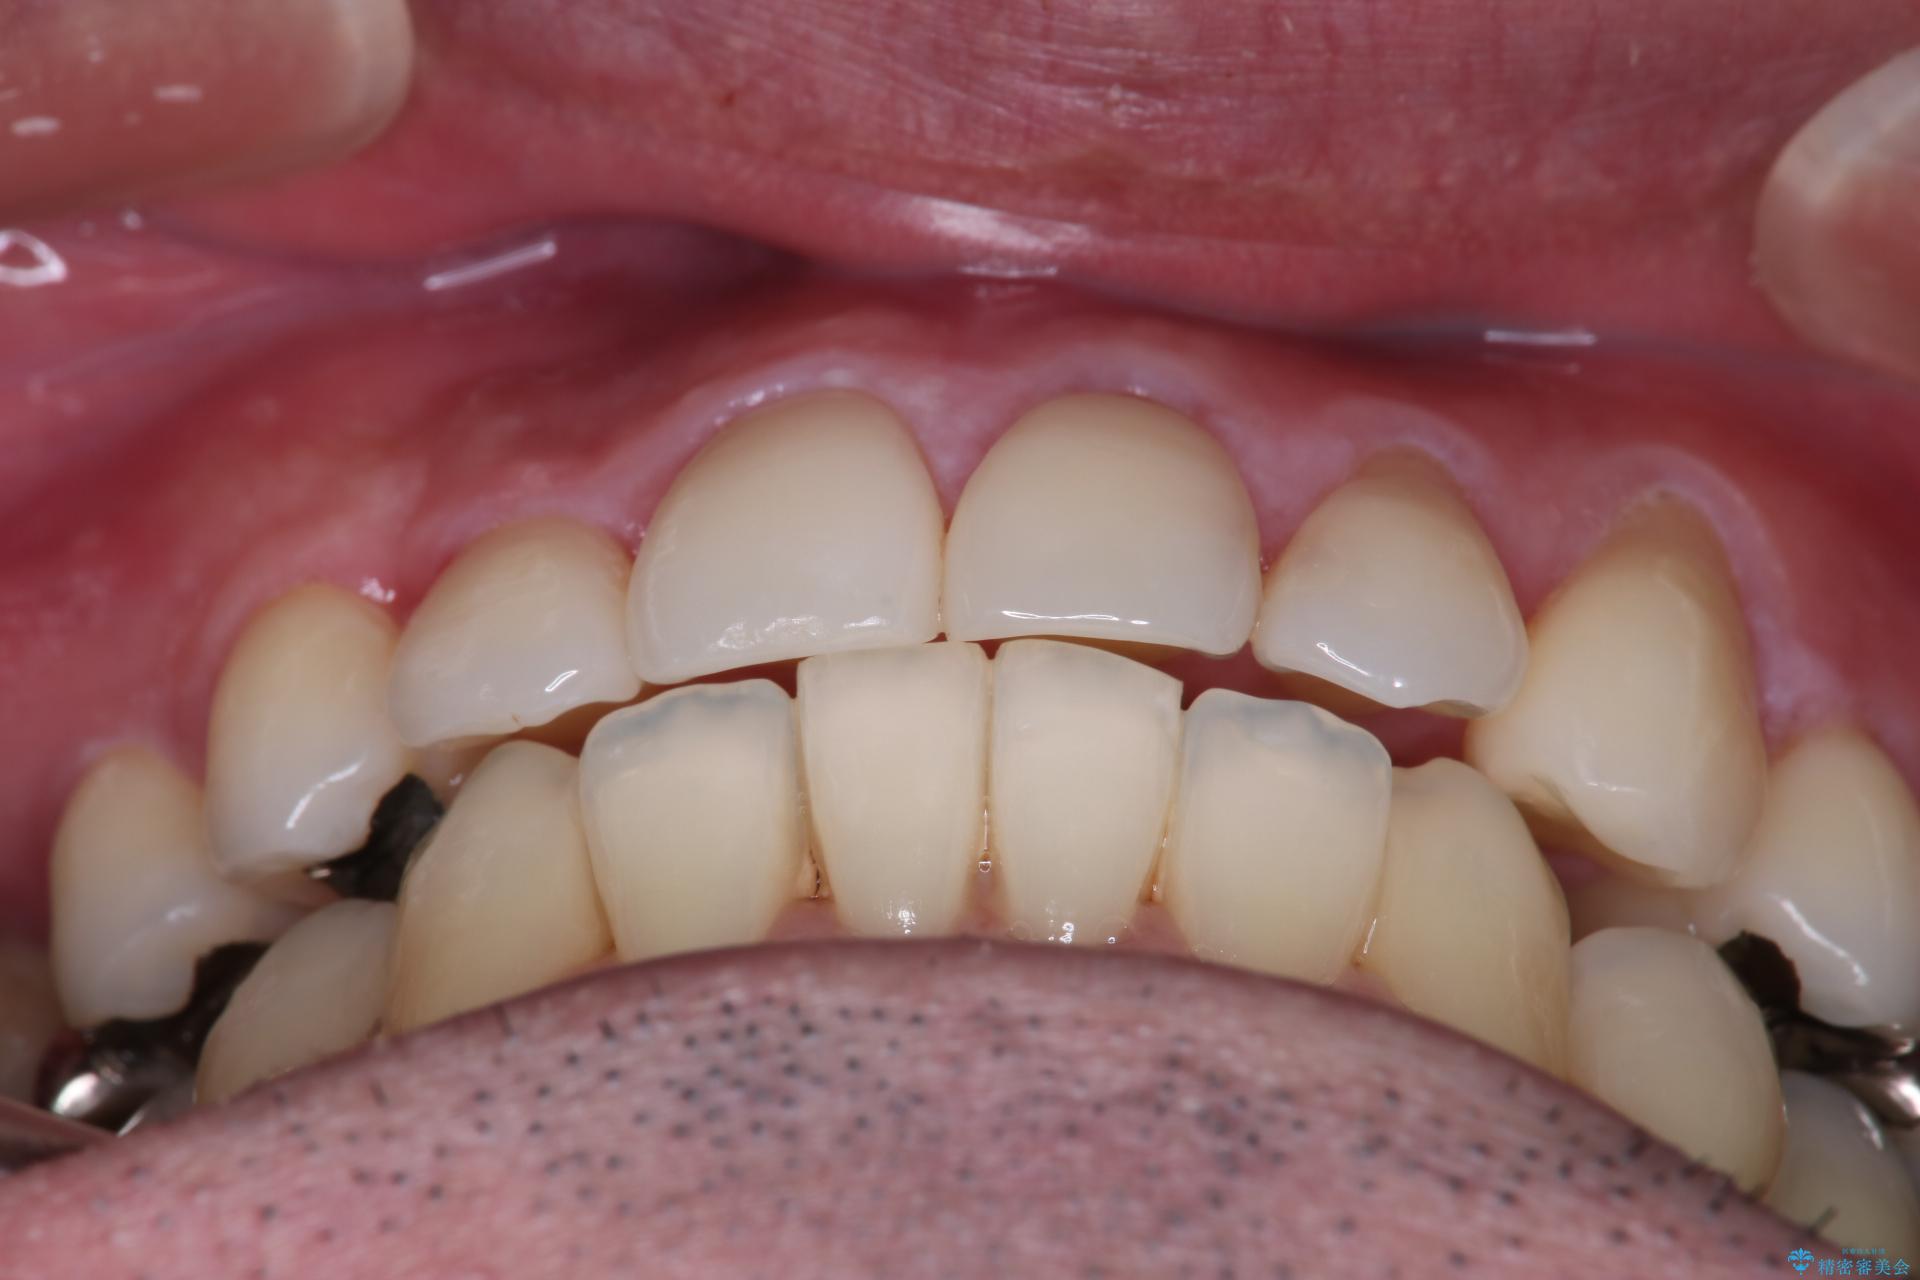

抜歯の本数を最小限に抑えたことで、治療計画も1年5ヶ月と短期間で終了することができ

主訴である前歯のがたつきも改善され綺麗な歯並びになりました。

矯正の装置を除去したタイミングで、ホワイトニングも行うことで歯の色味も白くなりました。